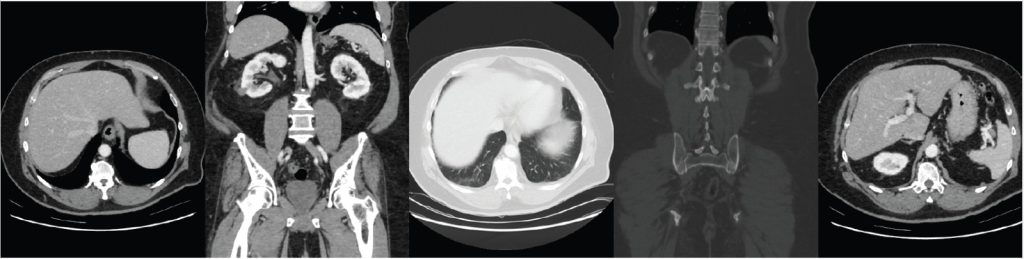

A CT Scan or Computed Tomography Scan is a diagnostic imaging technique that uses a series of X-rays to create detailed images of the inside of the body. It is more sophisticated and detailed than a standard x-ray as it is able to visualise a lot more details of the internal organs and structures that are not visible through a standard x-ray. CT scans are able to generate detailed images of organs, blood vessels, muscles, bones, and fat.

Once the required number of image slices have been achieved, the images are displayed individually or combined together to create a 3D image of the organ or structure. These slices of images allow the doctor to effectively locate the source of a disease or problem.

A CT scan can be done with or without a contrast. A contrast agent is a dye that allows soft tissues, blood vessels, and other less dense structures in the body to become highly visible in the scan results. Otherwise, a standard x-ray technology cannot effectively detect soft tissues and similar structures.

A CT in Singapore is usually done to diagnose various diseases and conditions of the body such as chest pain. It may also be used for guiding procedures. CT scan uses include the following: